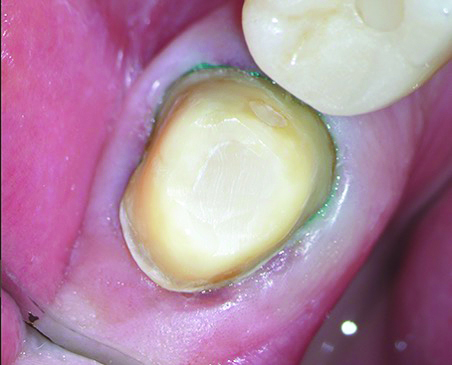

After removal of the rubber dam, final polishing was performed to ensure smooth margins and improve the longevity of the ceramic restoration. This step was carefully executed under the DOM with a fine-grit diamond flame bur to efficiently remove any excess cement post-cementation without damaging the restoration or tooth structure (Figure 20). The gingival retraction cords were then removed under the DOM to prevent soft-tissue trauma, with care taken to ensure that no cords were left trapped in the sulcus.

Fig 20. After removal of the rubber dam, the restoration margin was carefully fine-polished all around the tooth under microscopic guidance.

Figure 20